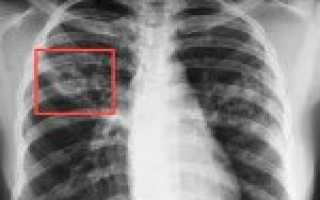

Туберкулема – различного типа заполненные каверны, на рентгене видны как округлые тени. Они бывают прогрессирующего, регрессирующего характера.

Кавернозный – диагностируется при обнаружении сформированного каверна (ложбина, впадина, ямочка) в легочных тканях.

• рентген легких – флюорография, рентгенография;

• рентгеноскопия;

• томография;

• Лучевая диагностика.Рентгенография легких является обязательным диагностической процедурой, позволяющей выявить характер изменений в легочной ткани (инфильтративный, очаговый, кавернозный, диссеминированный и т. д.), определить локализацию и распространенность патологического процесса. Выявление кальцинированных очагов указывает на ранее перенесенный туберкулезный процесс и требует уточнения данных с помощью КТ или МРТ легких.